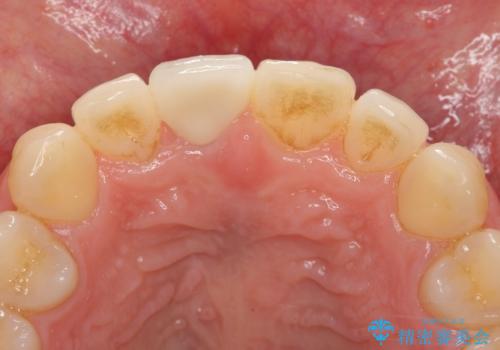

前歯の変色 打撲により失活した前歯の根管・セラミック治療

- 変色してきた前歯の形態回復、色調の改善を求めて来院されました。

X線検査、歯髄(歯の神経)の検査を行ったところ、失活(歯の神経の死んだ状態)であると診断されました。

放置すると変色が進行するだけでなく、根尖病変も形成される恐れが強いことから、根管治療を行ったのちセラミッククラウンによる審美性の改善を計画します。